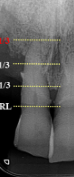

vertical bone loss

seen on radiographs as a non parallel line of bone loss

first sign of vertical bone loss

PDL space widens towards the crest

first radiographic sign of furcation involvement

pdl widening at furcation